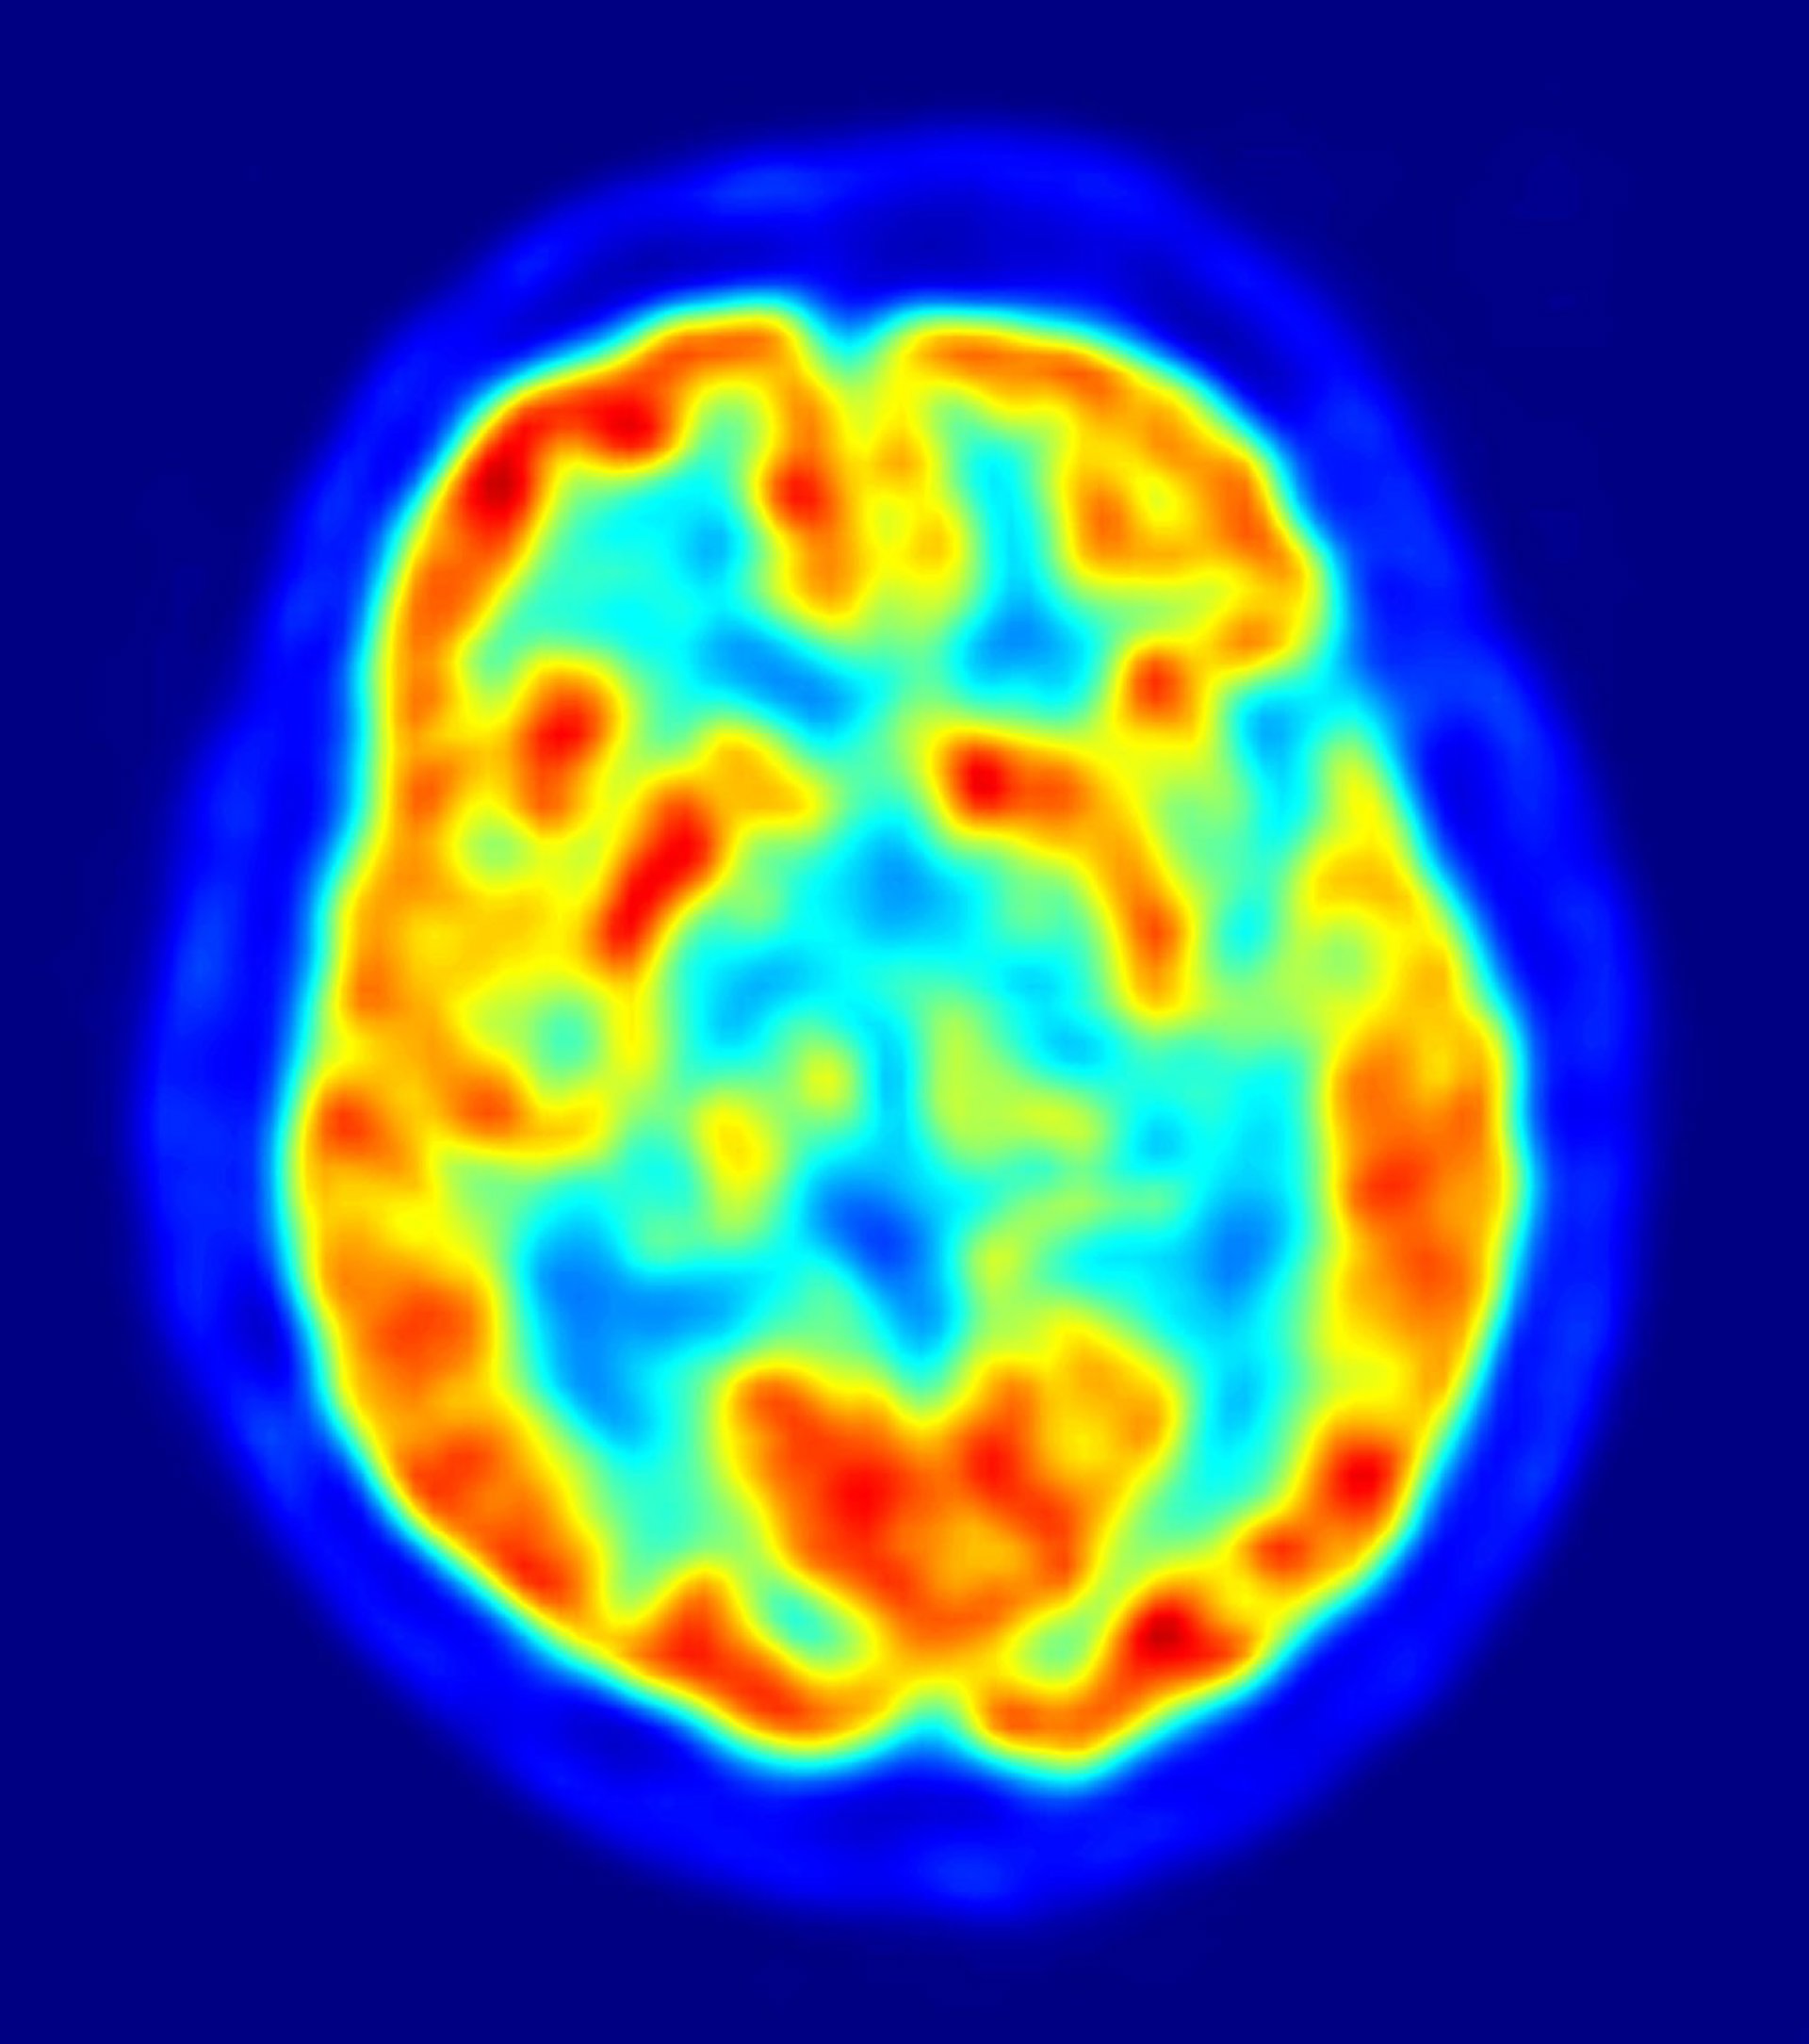

Los científicos suelen utilizar una técnica de imágenes cerebrales llamada resonancia magnética funcional (fMRI) para medir el mapa de activación aparentemente único de la visión en el cerebro de un individuo. Sin embargo, la prueba de fMRI requiere mirar a una pantalla intermitente durante varios minutos, mientras se mide la actividad cerebral, lo cual es una imposibilidad para las personas ciegas debido a enfermedades de los ojos. Ahora, el equipo de Penn ha resuelto este problema mediante la búsqueda de una descripción matemática común entre las personas de la relación entre la función visual y la anatomía del cerebro.

Los investigadores combinaron medidas tradicionales de resonancia magnética funcional de la actividad cerebral de 25 personas con visión normal, y después identificaron una relación estadística exacta entre la estructura de los pliegues del cerebro y la representación del mundo visual.